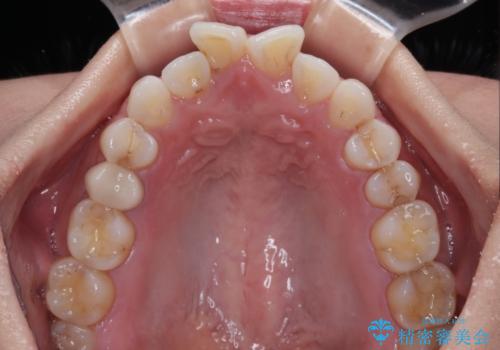

捻れた前歯を楽して改善 ワイヤー装置での非抜歯矯正

- 上下前歯のデコボコを気にして来院された患者様です。

ワイヤー矯正でもマウスピース矯正でも可能でしたが、短期間で、自身の手を煩わせることなく治療を行いたいとのことで、ワイヤー装置にて矯正治療を行うこととしました。

ご本人の中では2年近くかかるものと思っていたそうですが、1年で治療を終えることができ、大変満足していらっしゃいました。